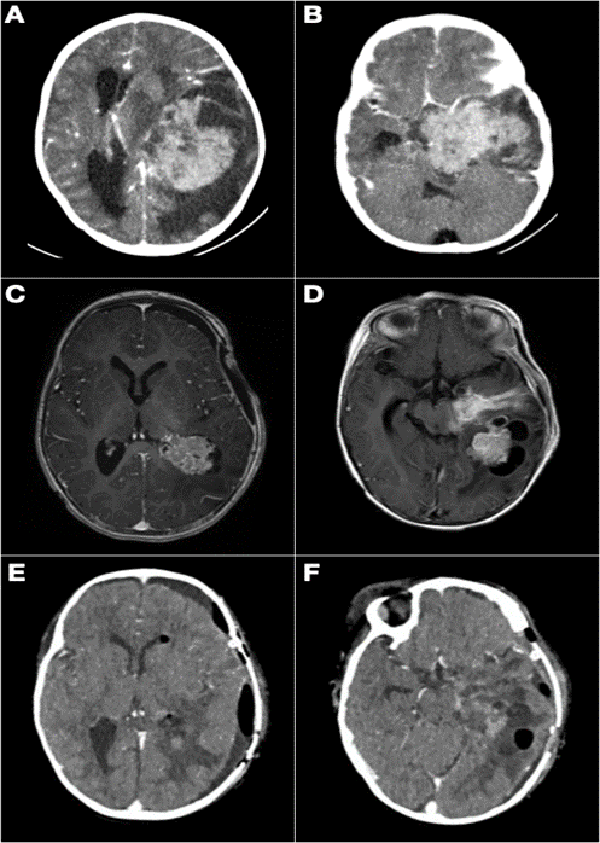

La resección parcial predominó en los grupos 1 (16 casos) y 2 (13 casos). De los 38 pacientes en los que se realizaron resecciones parciales 22 fueron lesiones supratentoriales, entre los cuales se encontraron 8 lesiones centro encefálicas (5 astrocitomas pilocíticos y pilomixoides, 1 craneofaringioma, 1 tumor embrionario indiferenciado y 1 hamartoma hipotalámico), 7 tumores de plexos coroideos (6 papilomas y 1 carcinoma de plexos coroideos) y 7 tumores hemisféricos. Por otro lado, 16 fueron lesiones infratentoriales (6 meduloblastomas, 3 teratoides rabdoides atípicos, 2 ependimomas anaplásicos, 3 astrocitomas pilocíticos, 1 pineoblastoma y 1 carcinoma de plexos coroideos). En la Figura 1 se muestran dos casos de abordajes a estos tumores.

Se realizó biopsia en 3 lesiones de tronco cerebral, 1 lesión pineal abordada endoscópicamente, 1 lesión hipotalámico-quiasmática, 1 lesión frontal subcortical y 1 lesión centroencefálica extensa. En los dos últimos casos se efectuó sólo biopsia por el intenso sangrado que obligó a suspender el procedimiento. El diagnóstico histológico fue tumor embrionario en ambos, por lo que se trataron con quimioterapia (Figura 5-B).

Figura 8: A y B) Paciente de 21 meses de vida, sexo femenino, que presentó hemiparesia faciobraquiocrural derecha, vómitos y deterioro del sensorio, TC de cerebro con contraste EV, lesión supra e infratentorial, con gran efecto de masa con compresión del tronco del encéfalo. Se realizó cirugía de exploración y exéresis parcial. Anatomía patológica informó papiloma de plexos coroideos. C y D) IRM de cerebro con contraste EV que evidenció resto tumoral intraventricular y en relación a cisternas peri mesencefálicas. Se realizó re exploración del tumor. E y F) Imagen por TC de cerebro con contraste EV postquirúrgica inmediata que evidenció exéresis total.